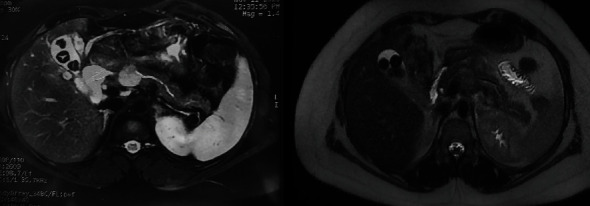

Iatrogenic aneurysms of the splenic artery constitute a rare yet potentially severe complication arising from diverse medical or surgical interventions. The clinical complexity and challenging management strategies associated with these aneurysms pose significant difficulties for clinicians. This circumstance is exemplified in our case report, detailing an iatrogenic aneurysm of the splenic artery that emerged secondary to a pancreatic fistula following a median pancreatectomy performed for a Frantz tumor. The intricate clinical presentation of this case underscores the considerable management challenges posed by such iatrogenic complications.